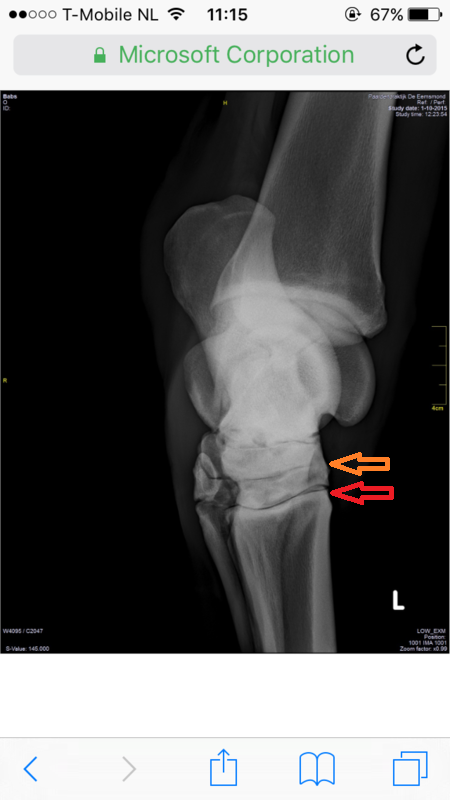

Babs was nooit makkelijk met haar achterbenen en soms ietwat stijf, maar toen ik haar heb laten keuren, bleek dit geen probleem. Ook de buigproef is ze doorgekomen en verder nooit kreupel geweest. Maar sinds eind augustus liep Babs kreupel, eerst hebben we het even aangekeken, maar het werd niet beter, daarom hebben we besloten haar op de foto te zetten, daar kwam uit dat ze spat heeft en een wat ernstigere vorm. Ook vertelde de dierenarts dat ze al spat had, maar dat, dat vergroeid is, waar ze nu last van heeft is "nieuwe" spat met botoplossingen. Babs loopt op het moment behoorlijk kreupel, maar is verder zichzelf, lekker actief en alert.

Foto's:

Voor degene die benieuwd zijn naar de foto's